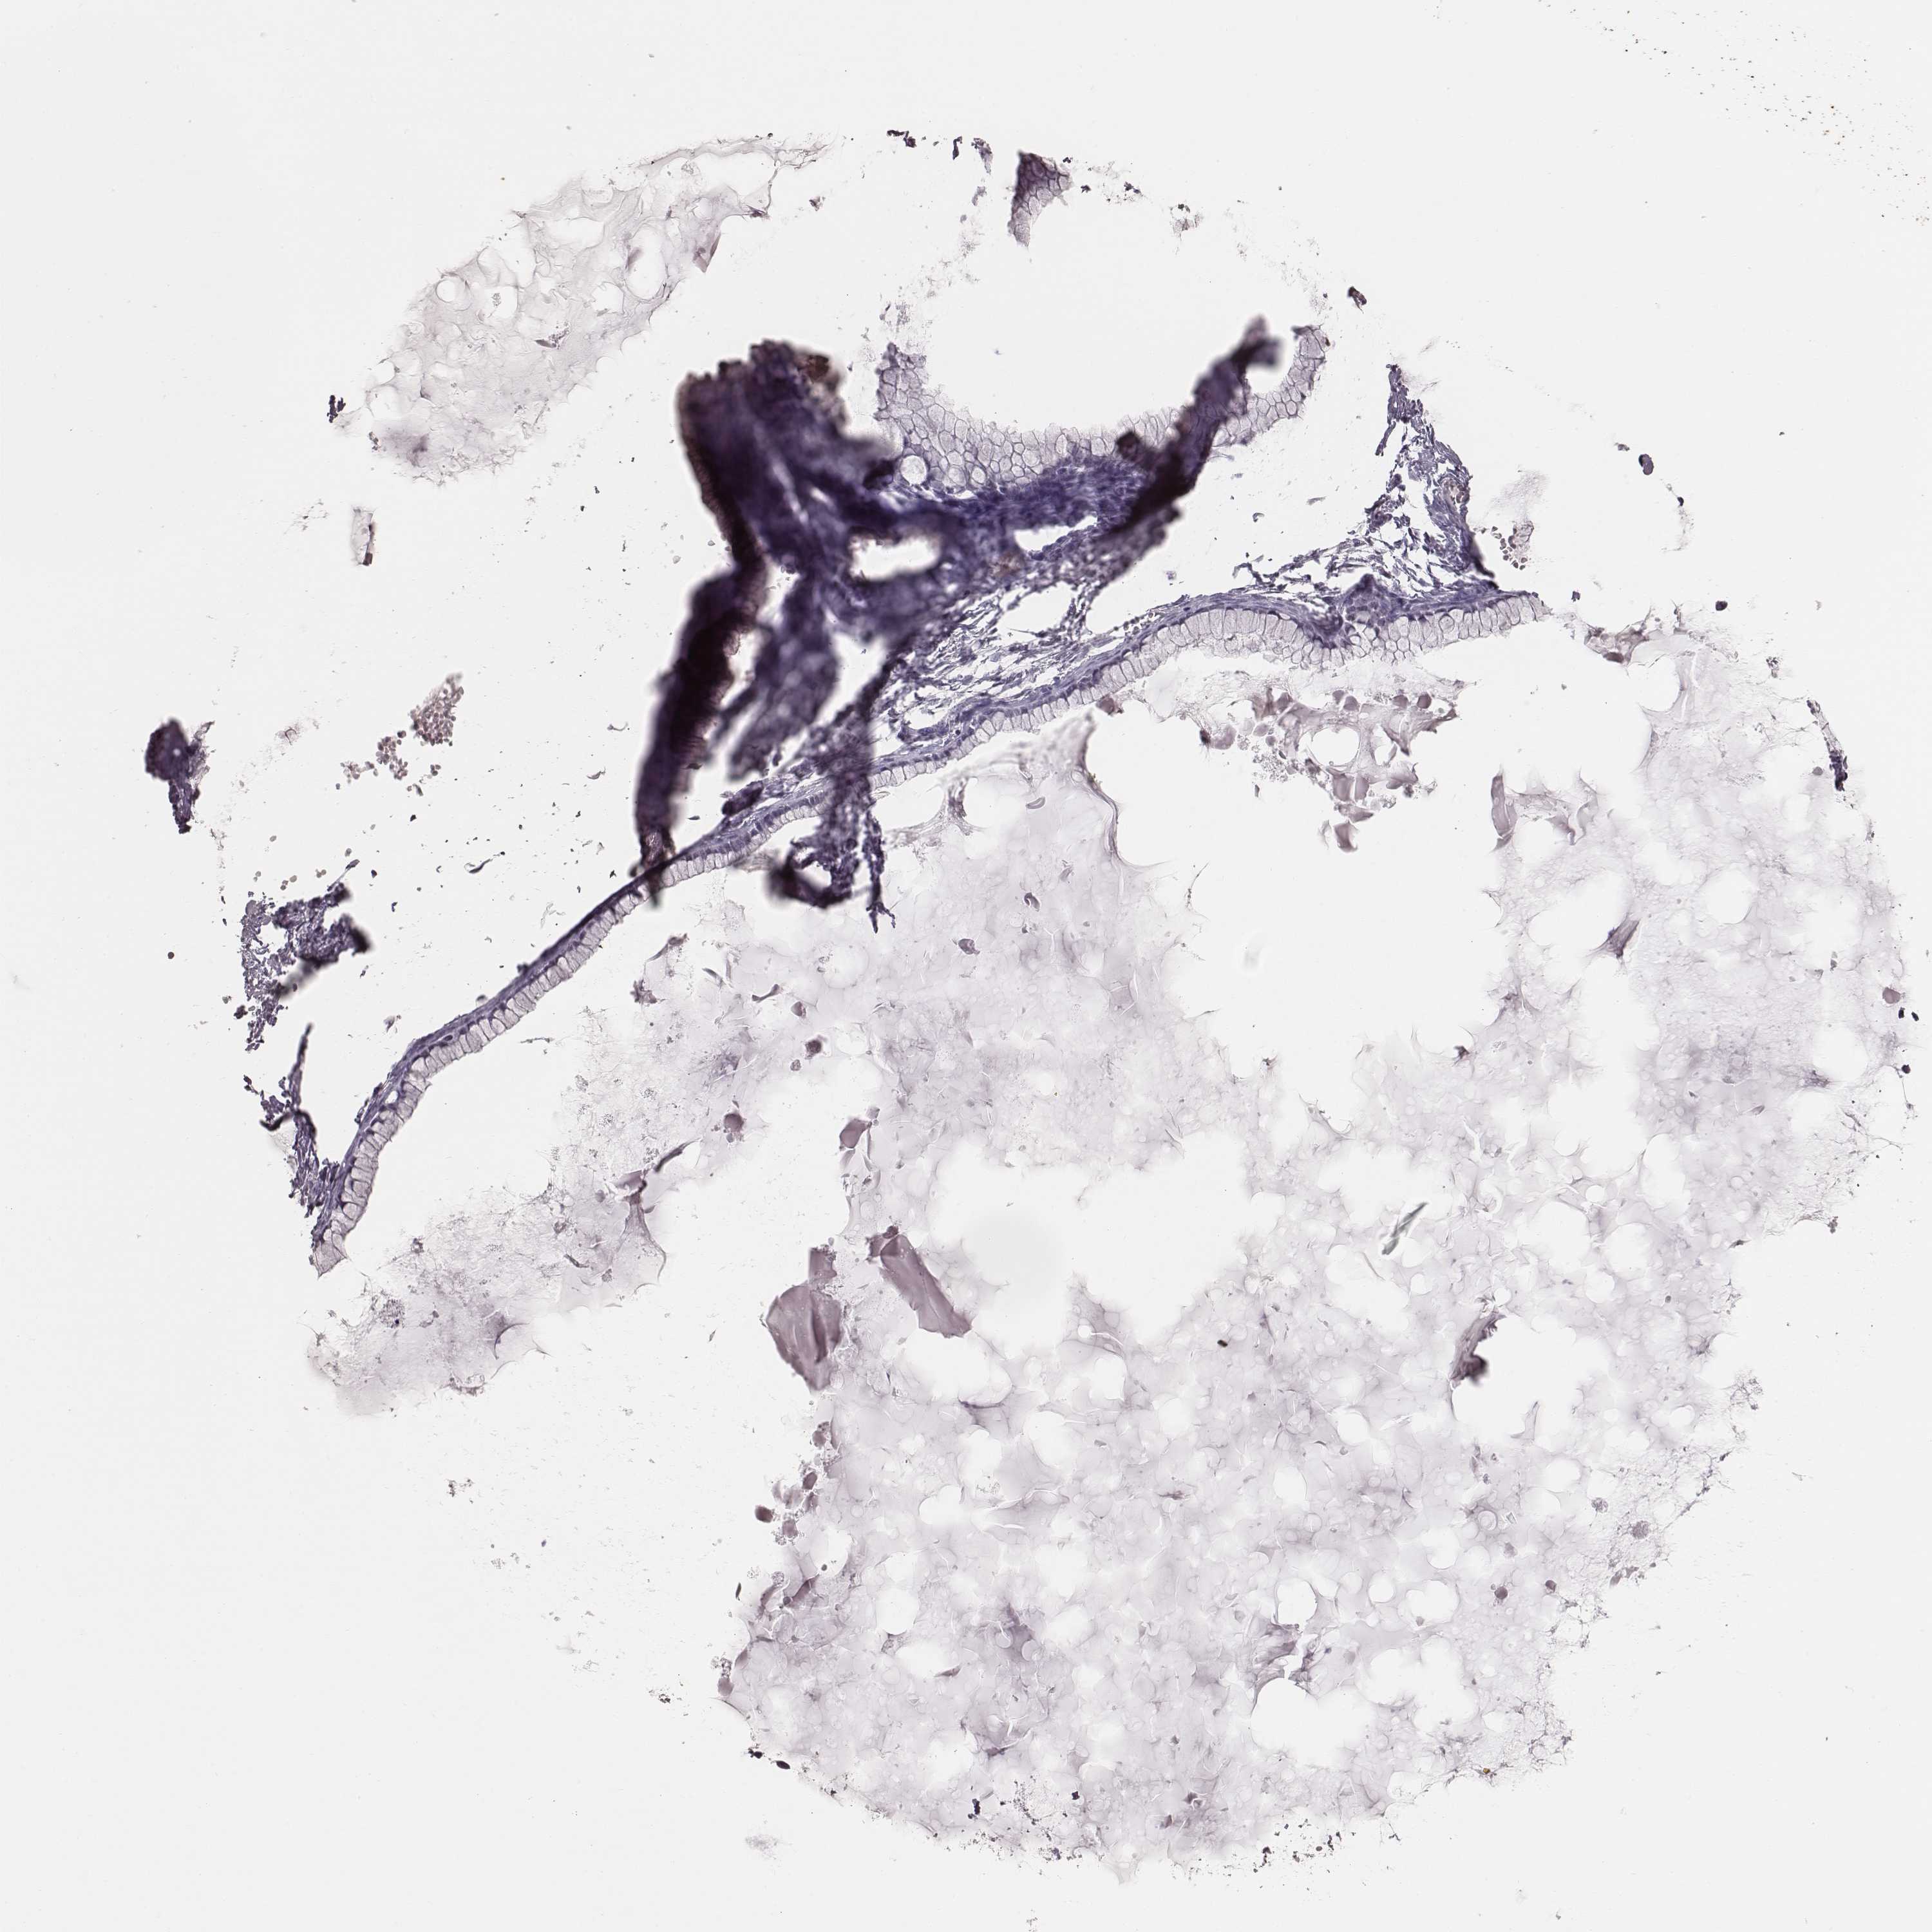

OVARIAN CANCER - Protein expressioni

A mouse-over function shows sample information and annotation data. Click on an image to view it in a full screen mode. Samples can be filtered based on level of antibody staining by selecting one or several of the following categories: high, medium, low and not detected. The assay and annotation is described here.

Note that samples used for immunohistochemistry by the Human Protein Atlas do not correspond to samples in the TCGA dataset.

Antibody stainingi

Antibody staining in the annotated cell types in the current human tissue is reported as not detected, low, medium, or high, based on conventional immunohistochemistry profiling in selected tissues. This score is based on the combination of the staining intensity and fraction of stained cells.

Each image is clickable and will lead to virtual microscopy that enables deeper exploration of all samples and also displays staining intensity scores, fraction scores and subcellular localization as well as patient and tissue information for each sample.

Antibody HPA070395

Staining

High

Medium

Low

Not detected

Intensity

Strong

Moderate

Weak

Negative

Quantity

>75%

75%-25%

<25%

None

Location

Nuclear

Cytoplasmic/membranous

Cytoplasmic/membranous,nuclear

Cystadenocarcinoma, serous, NOS

Cystadenocarcinoma, mucinous, NOS

Carcinoma, endometroid